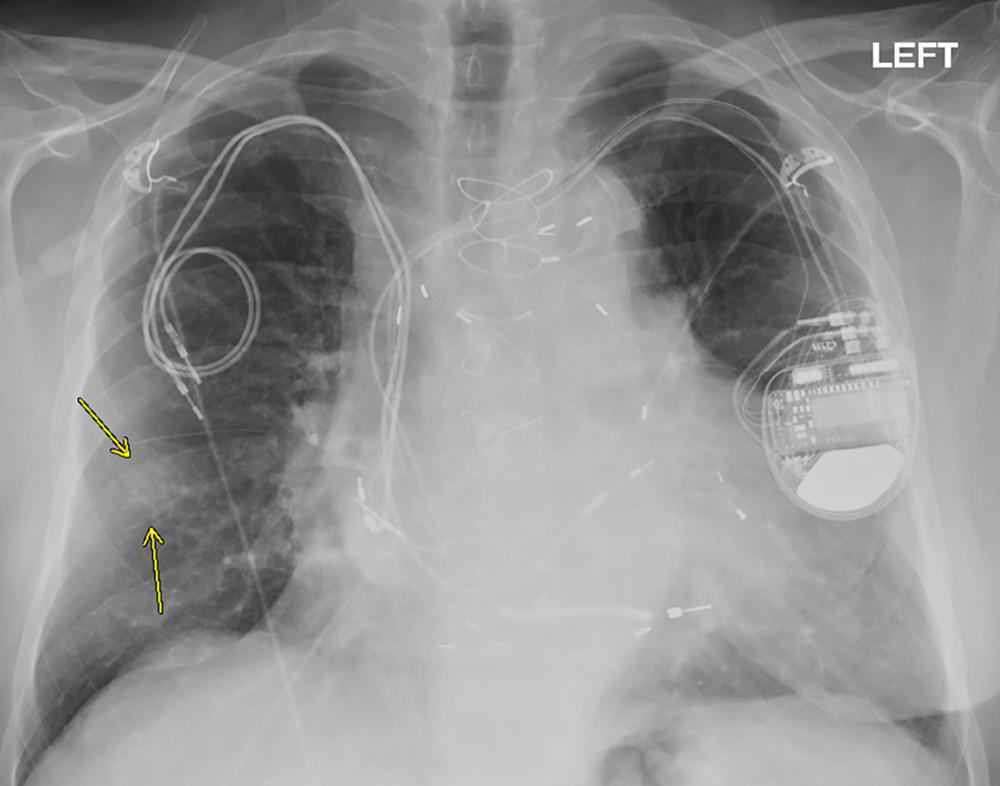

Figure 7. Chest radiograph, posteroanterior view, in a 79-year-old man with history of previous pacemaker, with abandoned right atrial and right ventricular pacing leads on the right side at time of new cardiac resynchronization therapy defibrillator implant on the left side. Arrows indicate a nodular opacity in the right midlung concerning for mass.